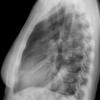

Case 2  Lingular pneum Lat

Date: 04/17/2005

Views: 7048